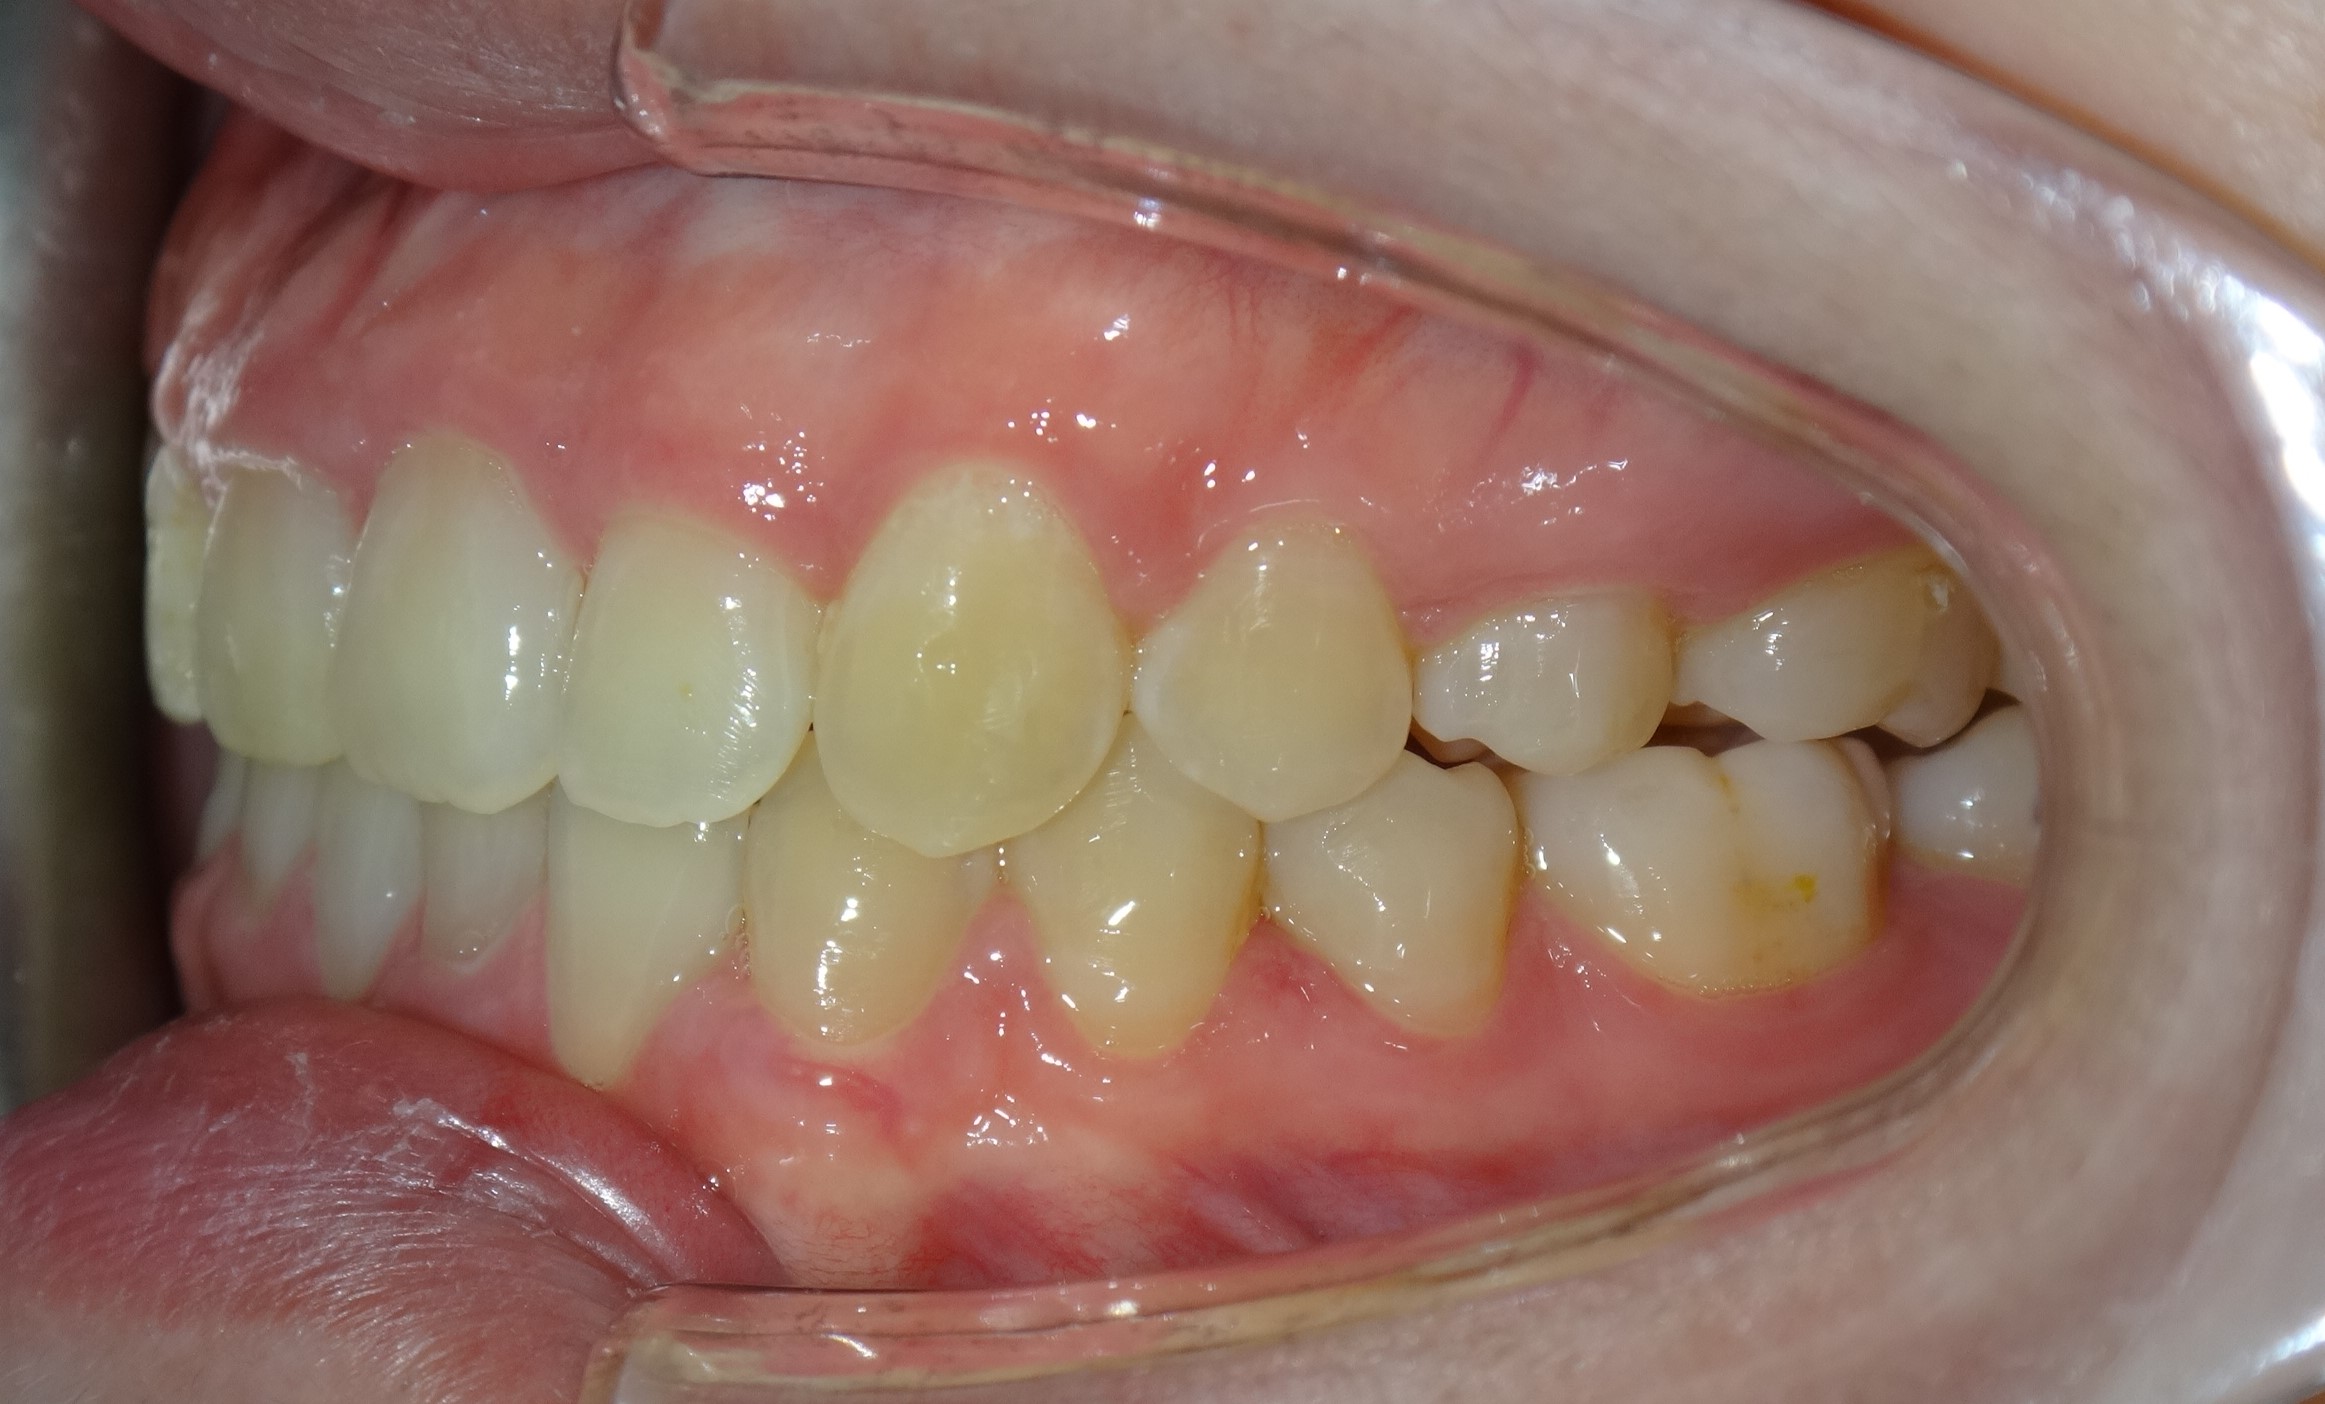

不拔牙案例 首頁 案例分享 齒顎矯正 不拔牙案例 - 矯正不拔牙案例 - 年紀:27歲 治療方式:隱適美隱形矯正 時間:34個月 主訴:前牙錯咬、排列不整 矯正前 矯正後 矯正前 矯正後 矯正前 矯正後 聲明:本所療程皆由專業醫生評估後,依照個人口腔狀況進行治療。因每位患者個別狀況不同,術後狀況也不盡相同,需親來本所由醫生評估。